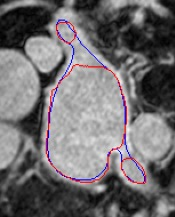

Automated segmentation in medical image analysis is a challenging task that requires a large amount of manually labeled data. However, most existing learning-based approaches usually suffer from limited manually annotated medical data, which poses a major practical problem for accurate and robust medical image segmentation. In addition, most existing semi-supervised approaches are usually not robust compared with the supervised counterparts, and also lack explicit modeling of geometric structure and semantic information, both of which limit the segmentation accuracy. In this work, we present SimCVD, a simple contrastive distillation framework that significantly advances state-of-the-art voxel-wise representation learning. We first describe an unsupervised training strategy, which takes two views of an input volume and predicts their signed distance maps of object boundaries in a contrastive objective, with only two independent dropout as mask. This simple approach works surprisingly well, performing on the same level as previous fully supervised methods with much less labeled data. We hypothesize that dropout can be viewed as a minimal form of data augmentation and makes the network robust to representation collapse. Then, we propose to perform structural distillation by distilling pair-wise similarities. We evaluate SimCVD on two popular datasets: the Left Atrial Segmentation Challenge (LA) and the NIH pancreas CT dataset. The results on the LA dataset demonstrate that, in two types of labeled ratios (i.e., 20% and 10%), SimCVD achieves an average Dice score of 90.85% and 89.03% respectively, a 0.91% and 2.22% improvement compared to previous best results. Our method can be trained in an end-to-end fashion, showing the promise of utilizing SimCVD as a general framework for downstream tasks, such as medical image synthesis and registration.